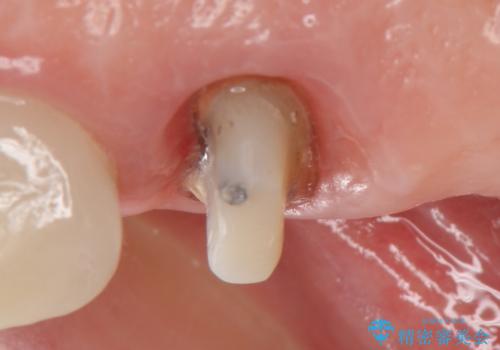

- アメリカの歯科医院にて治療途中の歯の仮歯が割れてしまったので診て欲しいといらっしゃった方の症例です。

しばらくアメリカに戻れそうにないため、当院での治療を希望。土台の築造まで処置は終わっているとのことだったのでオールセラミッククラウンによる補綴のみを行いました。

※遠心の欠損部はアメリカにてインプラント予定とのこと。